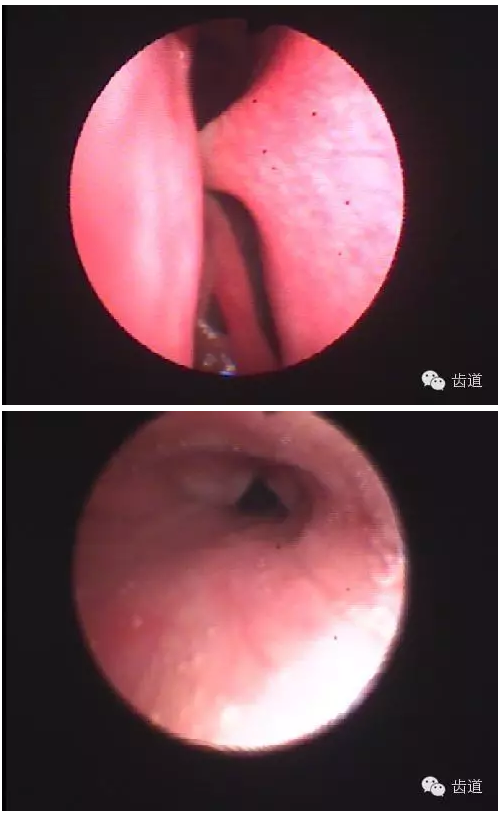

3.關(guān)節(jié)造影 主要是上腔造影

— 顯示關(guān)節(jié)盤移位,穿孔。

4.關(guān)節(jié)內(nèi)鏡檢查-直觀

可發(fā)現(xiàn)早期病變

CT斷層掃描

纖維鼻咽喉鏡檢查